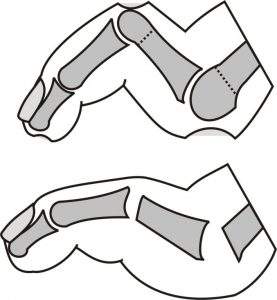

Der Charcotfuß durchläuft mehrere Stadien. Er beginnt mit einer Flüssigkeitsvermehrung (Ödem), was der Patient als Schwellung, teilweise auch als Rötung wahrnimmt. Trotz Schwellung und Rötung kann der Fuß wegen der Nervenschädigung schmerzfrei sein. Dieses Stadium darf nicht als Infektion fehlinterpretiert werden. Wird der Fuß in diesem Stadium entlastet, bildet sich diese „Knochenerweichung“ im Verlauf von 2 -3 Monaten deutlich und 6 – 12 Monaten vollständig zurück. Wird der Fuß allerdings normal belastet, schreitet der Knochenabbau bis zum kompletten Zusammenbruch voran. Bei einem Einbruch im Mittelfuß entsteht ein Plattfuß und später ein sog. Schaukel- oder Tintenlöscherfuß . Bei Befall des Sprunggelenks kann dessen normale Führung völlig aufgehoben sein, sodass die Patienten bisweilen auf dem Außen-oder Innenknöchel laufen.

In der Frühphase, Ödemphase, ist lediglich eine komplette Entlastung von 3 Monaten einzuhalten. Dies erfolgt in der Regel in einer speziellen Zwei-Schalen-Orthese oder in einem Total Contact Cast. Bei einem geringen, stabilen Einbruch erfolgt die Anlage von speziellen Schuhen, die den weiteren Einbruch verhindern, etwa im Mittelfuß durch Anbringen einer steifen Sohle mit einer stützenden Einlage. Damit kann sich der Knochen wieder festigen und die Ausbildung einer Fehlstellung verhindert werden.

- In vielen Fällen werden die Knochen in korrigierter Stellung aneinander gefügt, was zwar zu einer Einschränkung der Beweglichkeit führt, aber die volle Belastbarkeit nach der Heilung ermöglicht. Dies erfordert regelmäßig eine mehrwöchige Entlastungsphase und teilweise den Einsatz eines Fixateur externe.